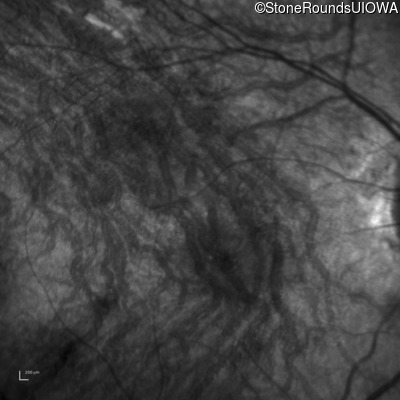

Infrared Fundus Photograph - Right - 10/300 sc

Exemplar